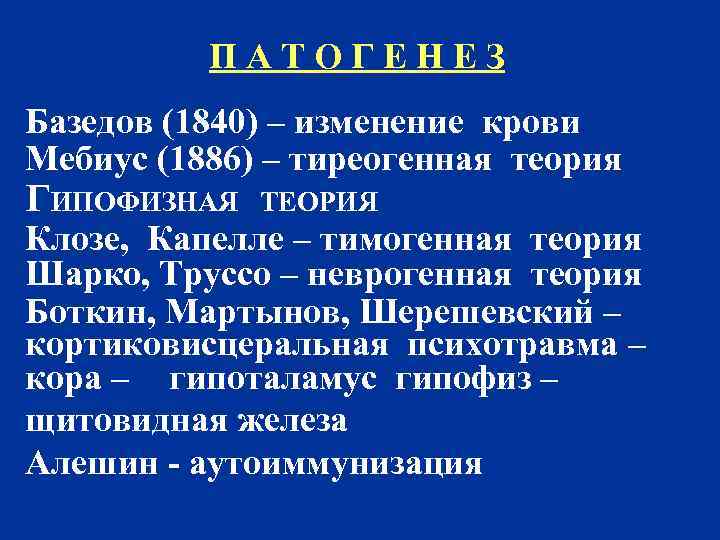

П А Т О Г Е Н Е З Базедов (1840) – изменение крови Мебиус (1886) – тиреогенная теория ГИПОФИЗНАЯ ТЕОРИЯ Клозе, Капелле – тимогенная теория Шарко, Труссо – неврогенная теория Боткин, Мартынов, Шерешевский – кортиковисцеральная психотравма – кора – гипоталамус гипофиз – щитовидная железа Алешин - аутоиммунизация

П А Т О Г Е Н Е З Базедов (1840) – изменение крови Мебиус (1886) – тиреогенная теория ГИПОФИЗНАЯ ТЕОРИЯ Клозе, Капелле – тимогенная теория Шарко, Труссо – неврогенная теория Боткин, Мартынов, Шерешевский – кортиковисцеральная психотравма – кора – гипоталамус гипофиз – щитовидная железа Алешин - аутоиммунизация